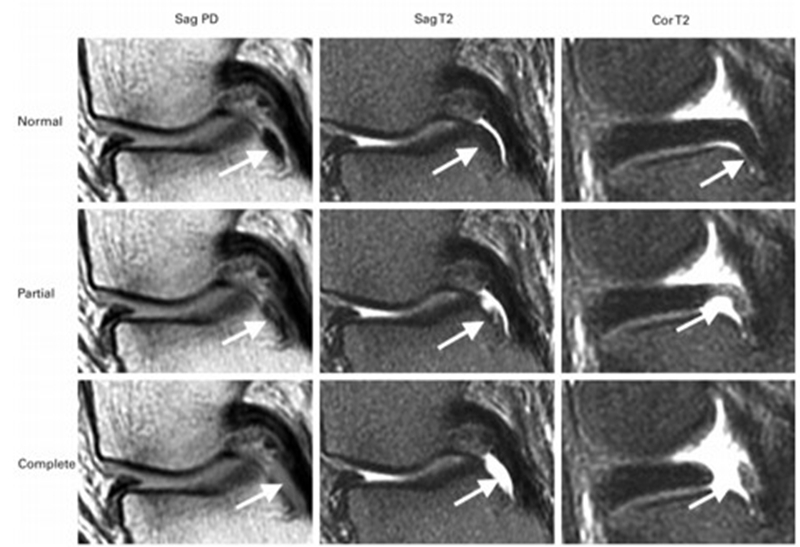

SONK与内侧半月板后根部损伤,有国外学者在SONK患者中通过MRI及关节镜检查,常可发现合并内侧半月板后根部的撕裂,该发生率可达到80%(24/30), 15例完全撕裂,9例部分撕裂。结果表明SONK可能与内侧半月板后根部撕裂后,导致股骨负重区的应力集中、软骨下骨髓水肿有关。

对于半月板损伤类型对SONK的影响,一项研究结果显示内侧半月板后根部撕裂组的半月板突出率为46.1%,平均坏死面积为423.1mm2。内侧半月板后角水平裂组的半月板突出率为35.3%,平均坏死面积为175.8mm2

与内侧半月板后角水平撕裂相比,后根撕裂将导致更大程度的突出和更广泛的骨坏死。